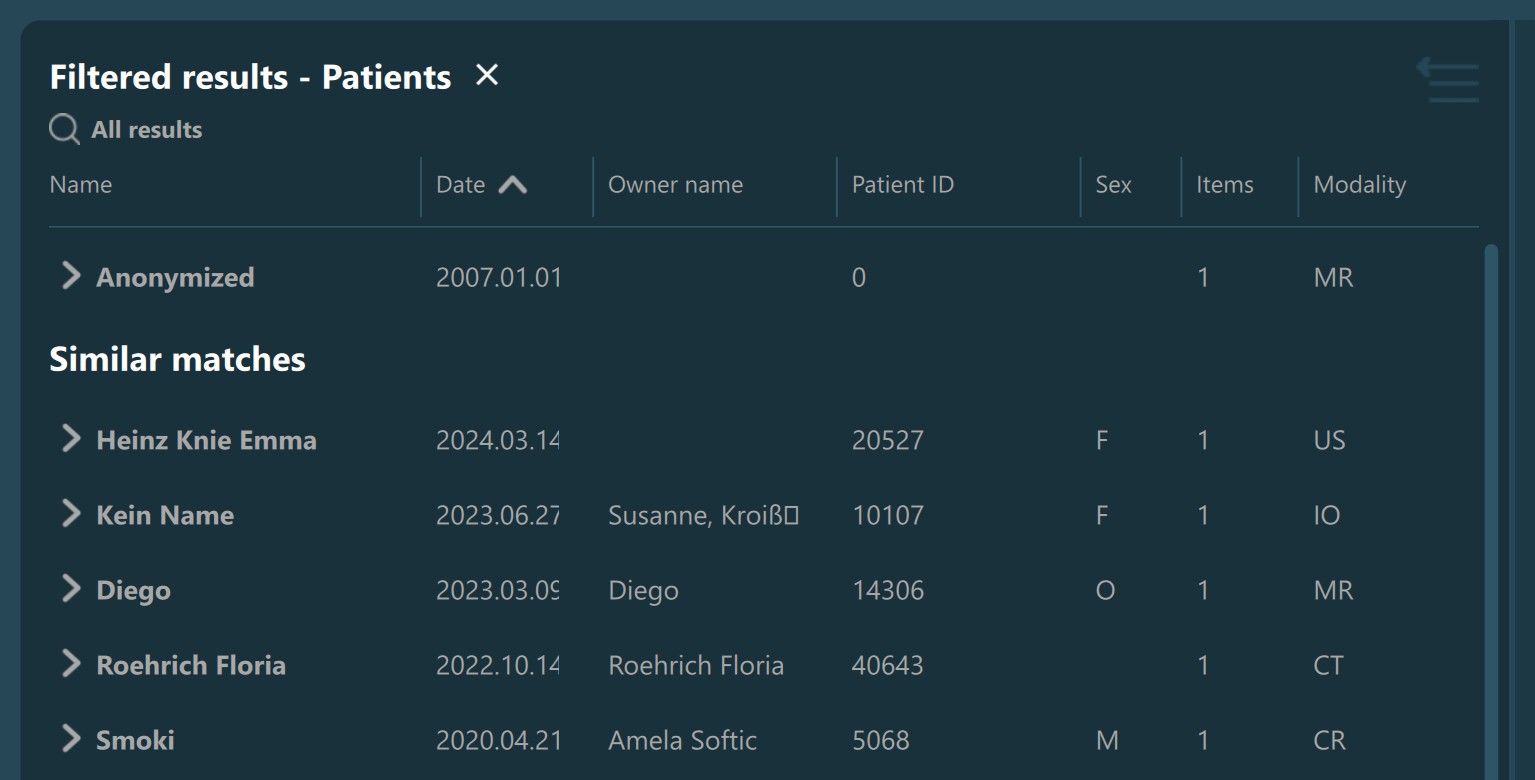

Patient name, Owner name, Patient ID: Use the input fields to specify the value of the following parameters. The Study List is automatically filtered after the initial filter timer has elapsed. When using these parameters, the studies in the Study List are separated into exact and similar matches.

Filtered Study List information with exact and similar matches found: